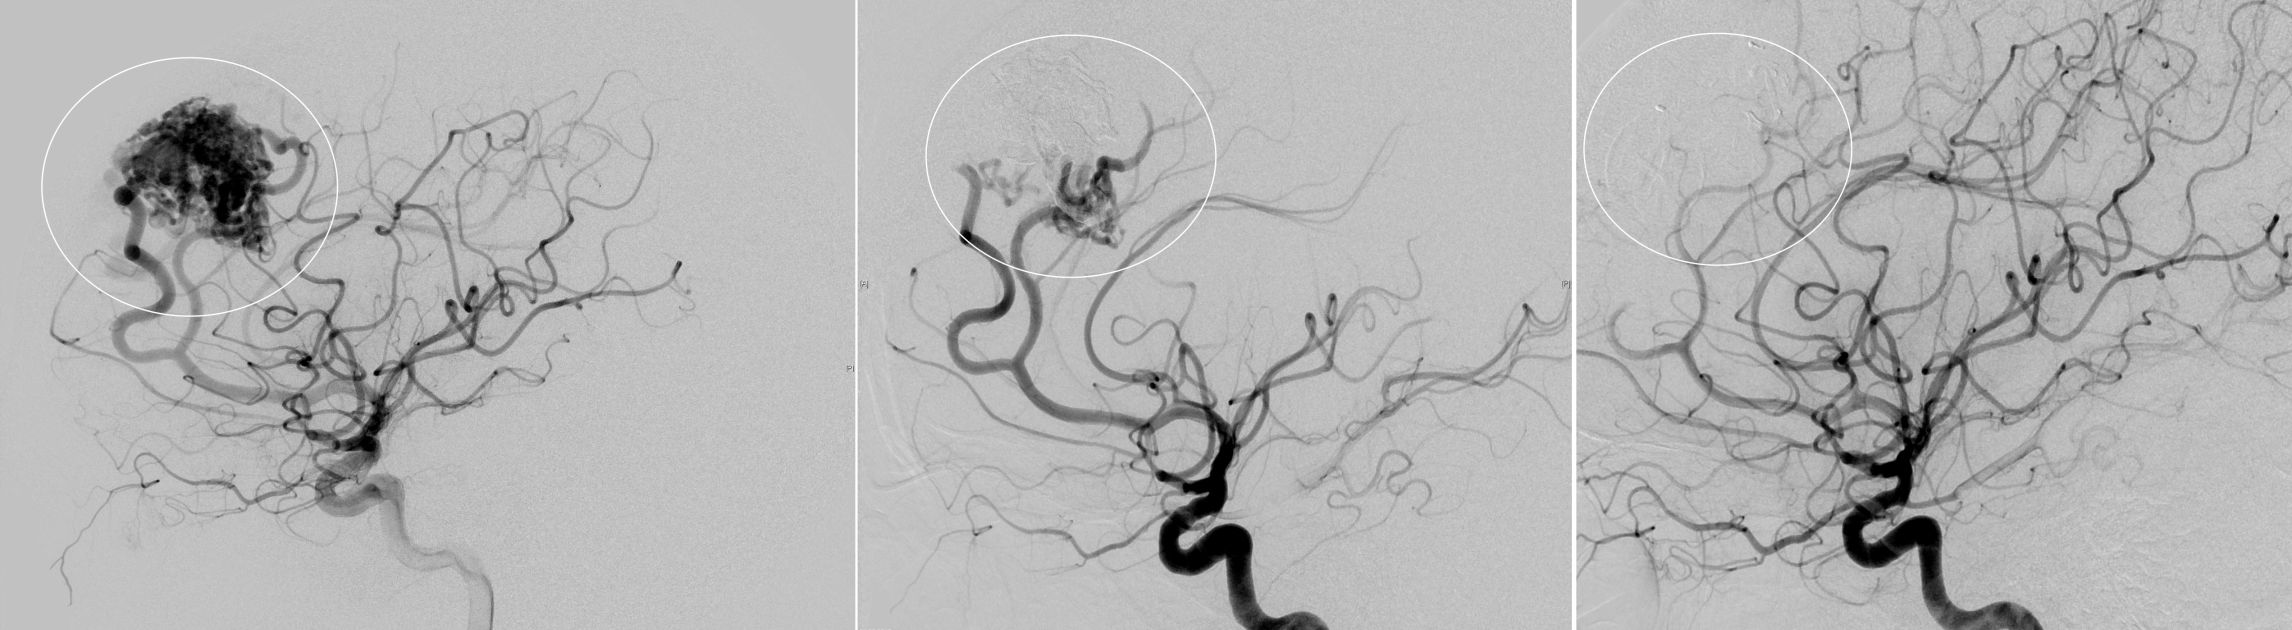

Zur Behandlung von arterio-venösen Malformationen stehen sowohl chirurgische, interventionelle, sowie auch kombinierte Therapieoptionen zur Verfügung. Bei der chirurgischen Therapie muss man mikrochirurgisch unter dem OP Mikroskop die gesamte AVM von den arteriellen Zuflüssen befreien, bevor man diese dann in toto entfernen kann. Bei der interventionellen Behandlung versucht man den Zufluss zur AVM zu reduzieren oder ganz zu verschließen indem man zumeist einen speziellen Flüssigklebstoff in die AVM appliziert. Hierbei muss stets darauf geachtet werden, dass die venöse Drainage bis zum Ende erhalten bleibt, da es sonst zu einer Einblutung kommen kann. Im Falle einer kombinierten Behandlung erfolgt häufig eine Teilembolisation der AVM in einem ersten Schritt, bevor dann im Anschluss chirurgisch die gesamte AVM entfernt wird.

Angiographische Darstellung einer AVM

Angiographische Darstellung einer AVM vor dem Therapiebeginn (links), nach erfolgreicher Teilembolisation (Mitte) und nach vollständiger mikrochirurgischer Resektion (rechts)